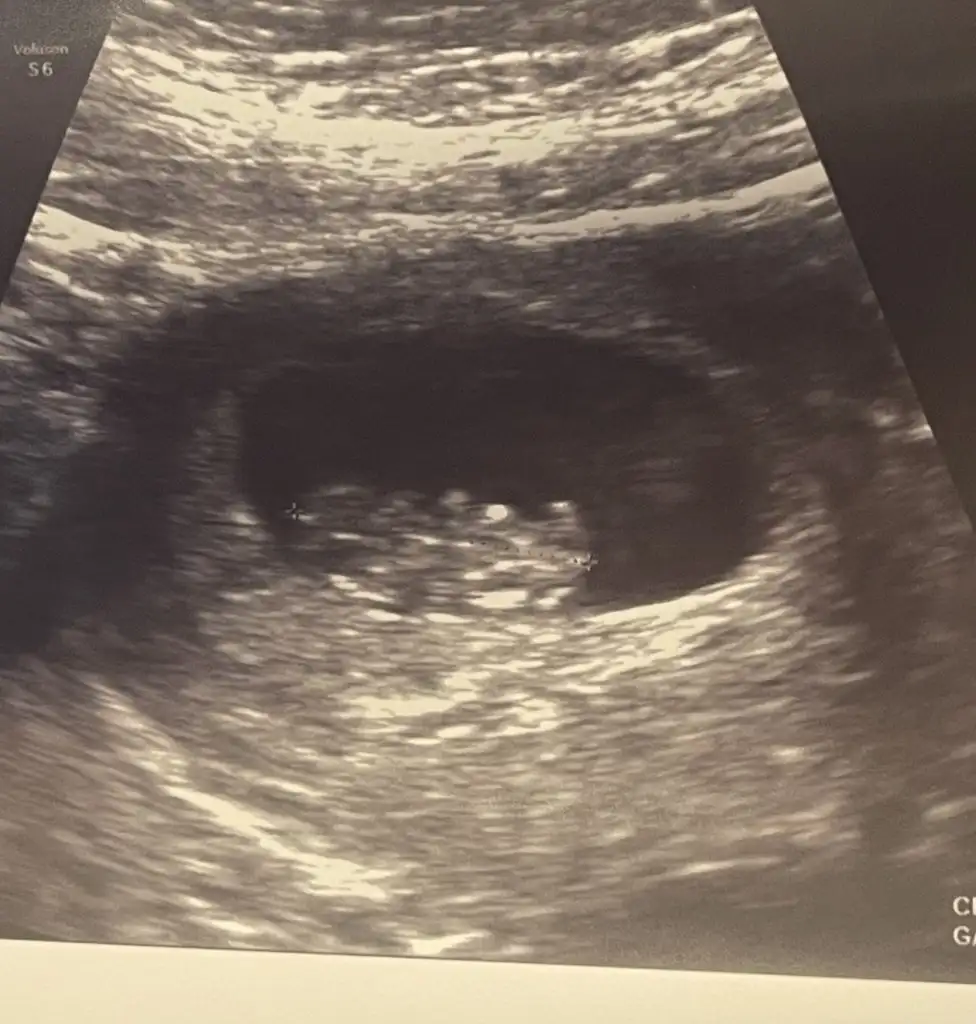

Ay maşallah ne kadar net 9+3 e göreSelam kızlar bizin bugün kontrolümüz vardı çok şükür her şey yolunda 9+3 görünüyor tam olarak

Teşekkür ederiz canım bizde şaşırdık vallaAy maşallah ne kadar net 9+3 e göre